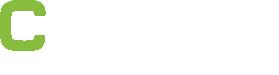

In the ongoing endovascular era, Thompson put forward, several innovations—including bioresorbable stents and non-invasive devices—have refined, or are set to refine, longstanding techniques and technologies. Indeed, the presenter said, there is “still room” for endovascular innovation despite the largely unchanging nature of its fundamental building blocks. However, these innovations will not, in Thompson’s view, ‘change everything’ in vascular surgery. Instead, he argued that the next paradigm shift in the field will be defined by the accelerated pace of technological change that is happening in the wider world.

Positive six-month findings from the randomised arteriovenous (AV) fistula arm of Merit Medical’s Wrapsody arteriovenous access efficacy (WAVE) pivotal trial have been revealed. The data were shown at the Cardiovascular and Interventional Radiological Society of Europe (CIRSE) annual congress (14–18 September, Lisbon, Portugal) during a FIRST@ CIRSE presentation. Wrapsody is a cell-impermeable endoprosthesis which is intended to extend long-term vessel patency in dialysis patients.